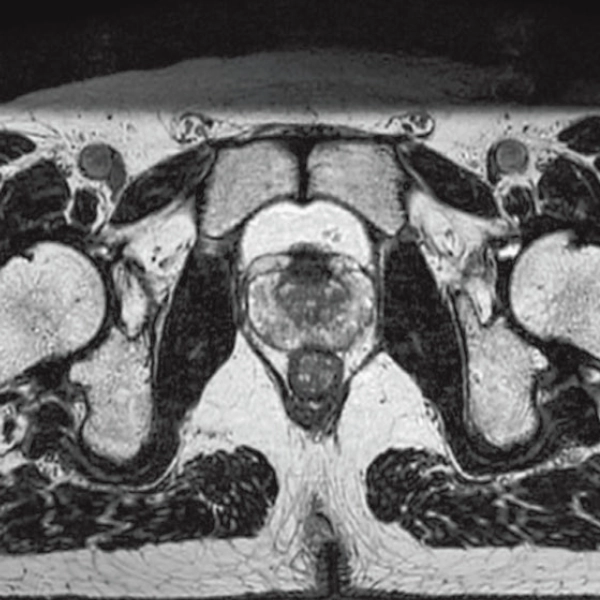

StillShot:The camera detects motion and suppresses the effects of body movement

FLAIR

T1WI Dual Echo (Out) Breath hold

RADAR:Body movement suppression technology for those who cannot hold still

T2*WI RADAR, 2:34

T2WI FatSat Respiratory gating RADAR, 2:16